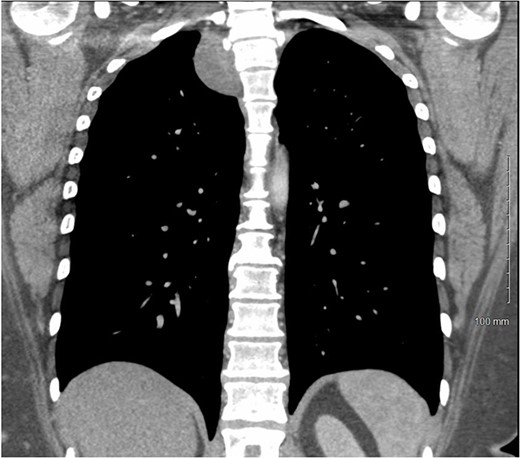

A 36-year-old female presented to an outside emergency department reporting chest pain, dizziness and abdominal pain for 7 hours. A computed tomography (CT) angiogram of the chest revealed a right paraspinal 4.2 × 2.8 × 3.3-cm cystic mass at the level of T2-3, which was well-circumscribed (Figs 1 and 2).

CT chest with IV contrast coronal view of right T2-T3 paravertebral mass.